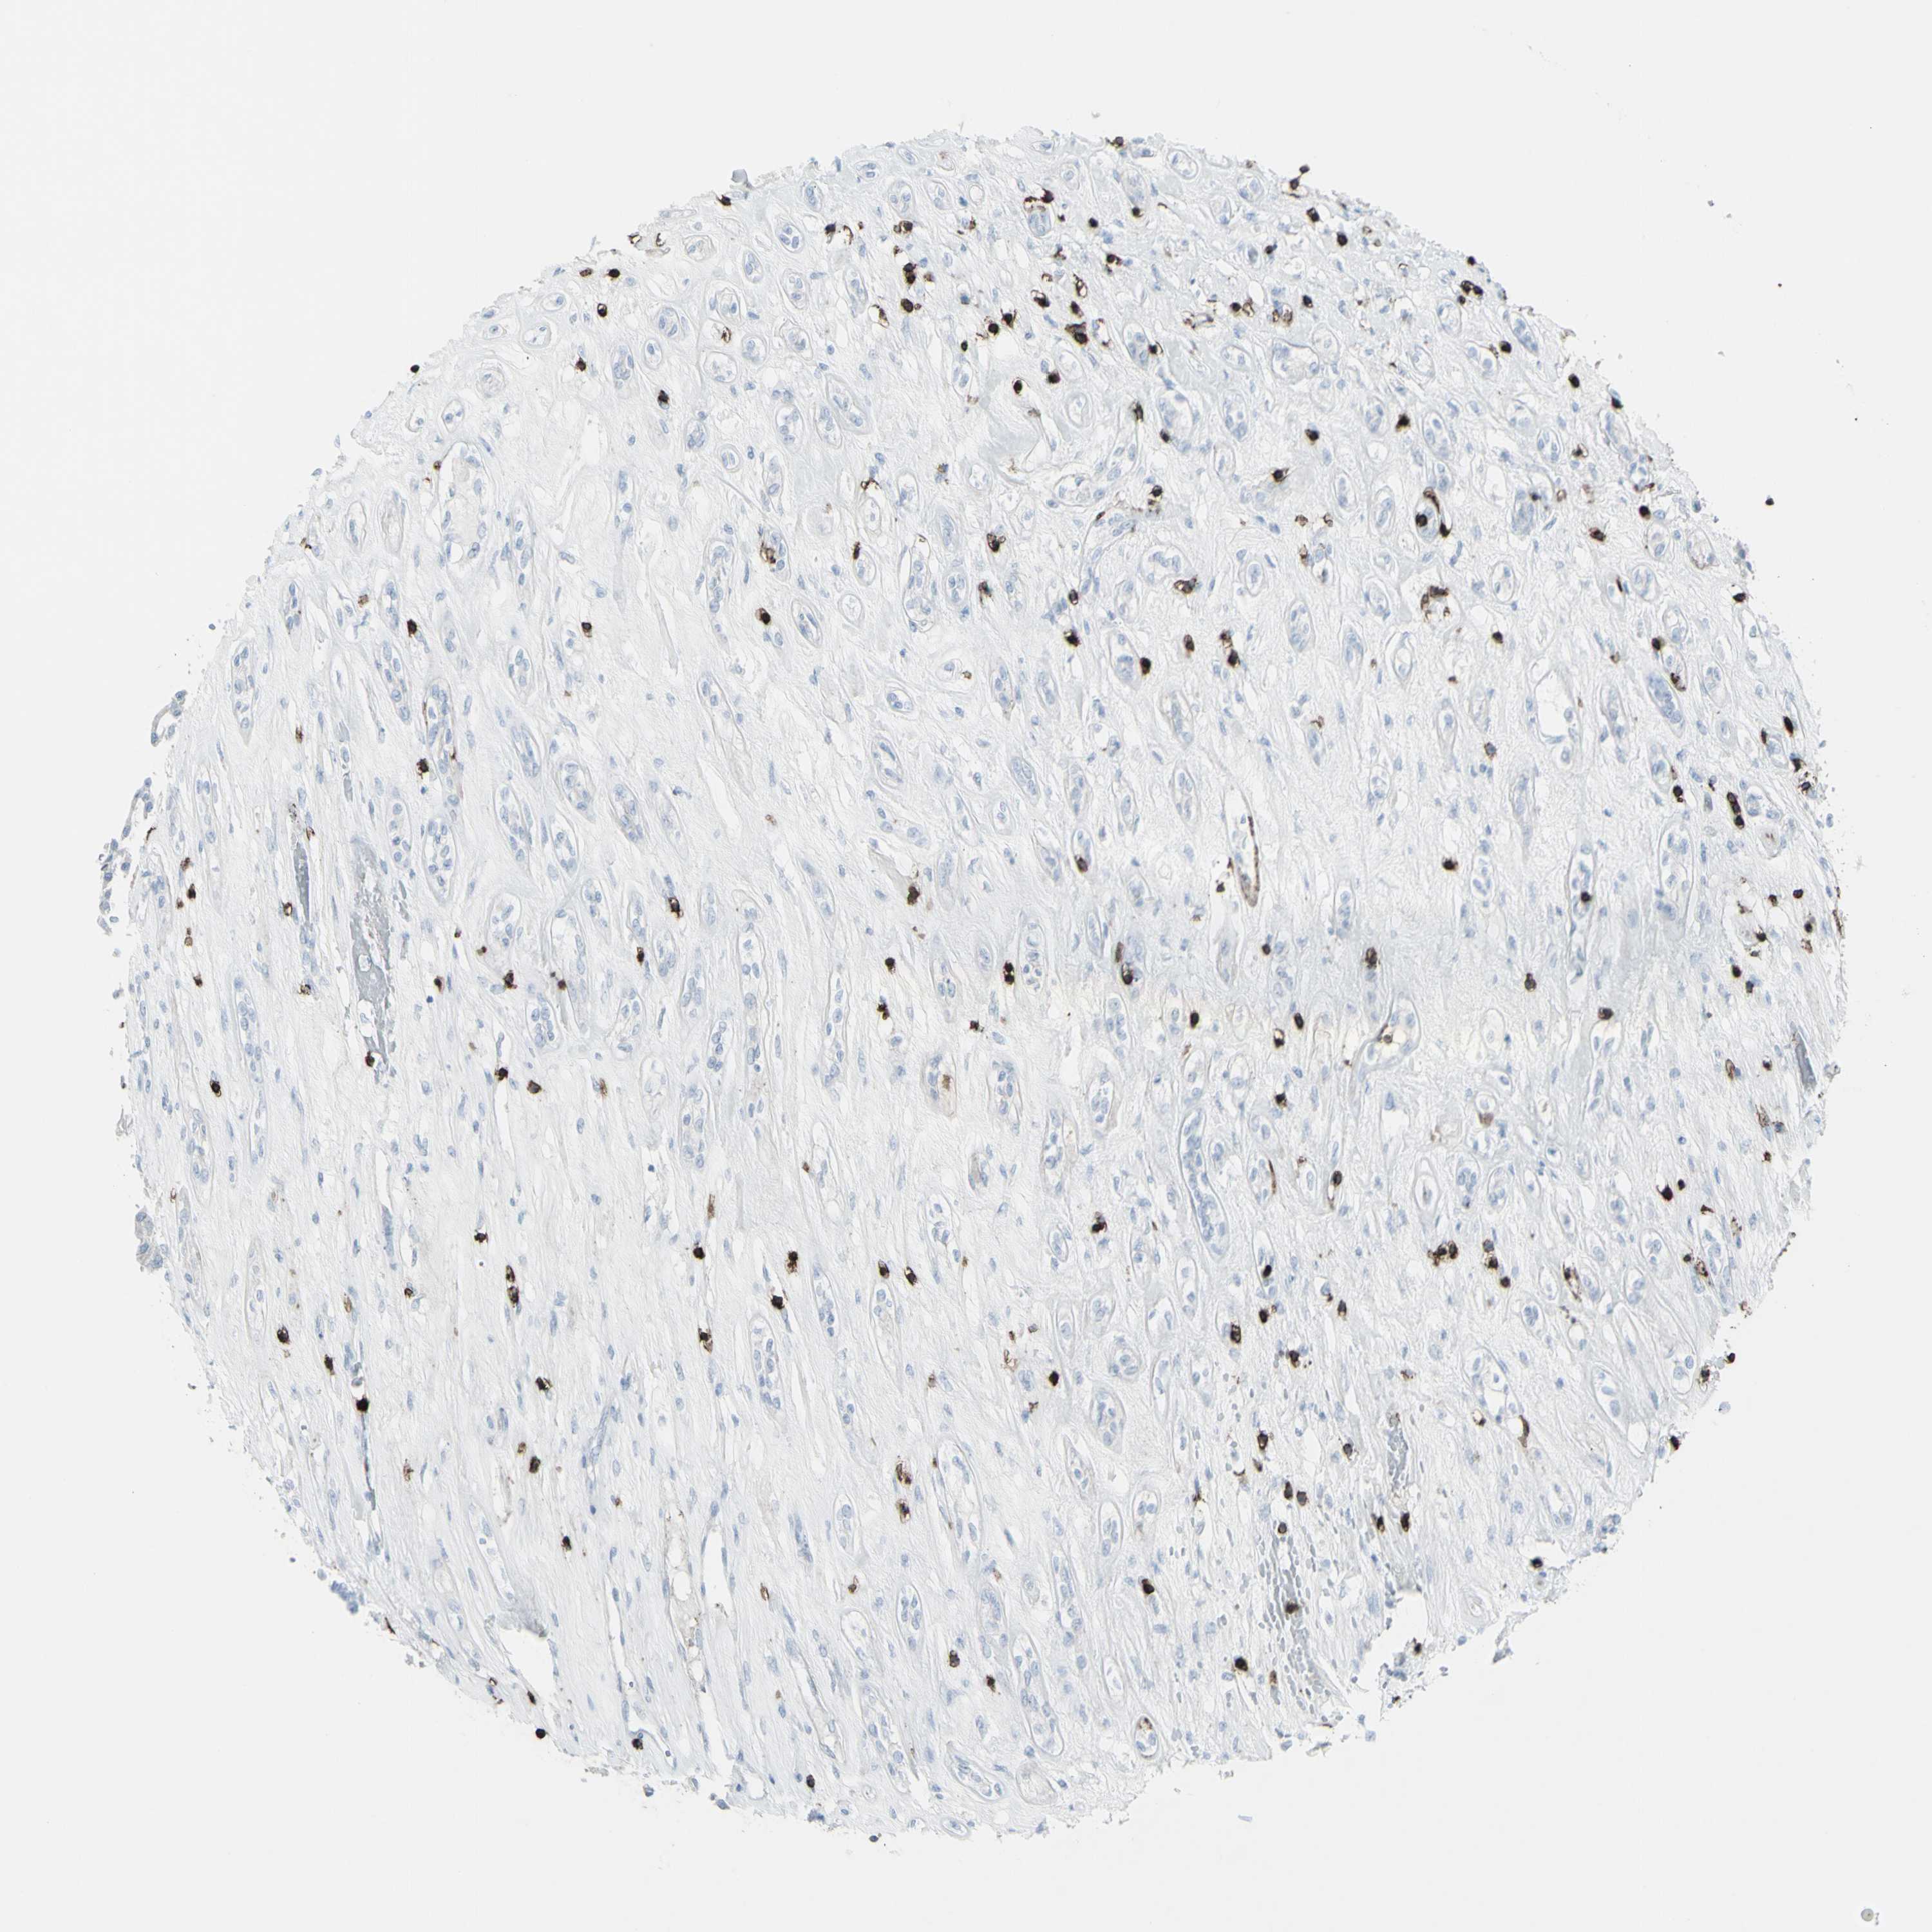

KIDNEY RENAL PAPILLARY CELL CARCINOMA (TCGA) - Interactive survival scatter ploti

The Survival Scatter plot shows the clinical status (i.e. dead or alive) for all individuals in the patient cohort, based on the same data that underlies the corresponding Kaplan-Meier plots. Patients that are alive at last time for follow-up are shown in blue and patients who have died during the study are shown in red.

The x-axis shows the expression levels (FPKM) of the investigated gene in the tumor tissue at the time of diagnosis. The y-axis shows the follow-up time after diagnosis (years). Both axes are complimented with kernel density curves demonstrating the data density over the axes. The top density plot shows the expression levels (FPKM) distribution among dead (red) and alive patients (blue). The right density plot shows the data density of the survived years of dead patients with high and low expression levels respectively, stratified using the cutoff indicated by the vertical dashed line through the Survival Scatter plot. This cutoff is automatically defined based on the FPKM cutoff that minimizes the p-score. The cutoff can be changed by dragging the vertical line or by entering a cutoff value in the square labeled "Current cut-off".

Under the Survival Scatter plot the p-score landscape (black curve; left axis) is shown together with dead median separation (red curve; right axis). Dead median separation is the difference in median mRNA expression between patients who have died with high and low expression, respectively. It is calculated as follows: median FPKM expression of dead patients with high expression - median FPKM expression of dead patients with low expression. This is intended to aid the user in visually exploring custom cutoffs and the associated p-scores and dead median separation.

Individual patient data is displayed and can be filtered by clicking on one or more of the category buttons on the top of the page. Categories describing expression level and patient information include: high, low, alive, dead, female, male and tumor stages. The scale of the x-axis can be toggled between linear and log-scale by clicking on the "x log" button. Mouse-over function shows TCGA ID, patient information and mRNA expression (FPKM) for each patient.

& Survival analysisi

Kaplan-Meier plots summarize results from analysis of correlation between mRNA expression level and patient survival. Patients were divided based on level of expression into one of the two groups "low" (under cut off) or "high" (over cut off). X-axis shows time for survival (years) and y-axis shows the probability of survival, where 1.0 corresponds to 100 percent.

CD247 is not prognostic in Kidney Renal Papillary Cell Carcinoma (TCGA)

Best expression cut offi

Based on the FPKM value of each gene, patients were classified into two groups and association between prognosis (survival) and gene expression (FPKM) was examined. The best expression cut-off refers the FPKM value that yields maximal difference with regard to survival between the two groups at the lowest log-rank P-value. Best expression cut-off was selected based on survival analysis .